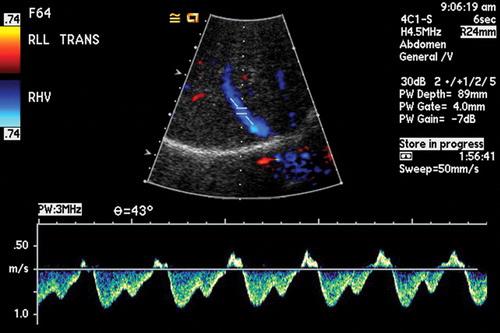

Permiteevaluarnosololosdiversosórganos delcuerpocomoeltejidocerebral,sino tambiénlosvasossanguíneos.Seutilizaen estudiosderutinaparaanalizarelcuello,cere‐bro,tóraxylosdiferentesórganosdelabdo‐men,asícomoloshuesos.Susoftwarepermi‐teprocesarreconstrucciones3Dcongráficos derealidadvirtualdeexcelentecalidad,que sondegranutilidadparaclínicosycirujanos. Conestatecnologíasereduceladosisde radiaciónenhastaun80%,estolohaceuna excelenteopciónenpacientespediátricosy adicionalmentesoportahasta205kgdepeso, muyútilenpacientesbariátricos.

Estáequipadoconunagrancantidadde aplicacionessofisticadasqueabarcan especialmenteestudioscardiovasculares:Se puedeevaluarelcorazón,analizarmediante angiotomografíacoronariasusarteriasyrea‐lizarprotocolosparapacientesaquienesse lesplanearealizarunreemplazovalvular.Tie‐neunaresoluciónespacialquebrindamejor definicióndeimagenenestudioscomo angiotomografíademiembrospélvicos, angiotomografíaaórtica,angiotomografía cerebral,angiotomografíadetroncossupra‐aórticos,loquepermitediagnosticaryplanifi‐carlosprocedimientosencasoscomoaneu‐rismas,estenosisoanomalíasvasculares. Cuentaconherramientasfuncionalescomo perfusióncerebralyesposiblerealizarestu‐dioscomotomografía,colonoscopíavirtual, enteroUrotomografía.

Lasangiografíasdiagnósticasnosayudana analizarlaanatomíadelasarteriasyvenas quellevanlasangrealosórganos,comolo sonelcerebro,lasextremidadesoelintestino. Enocasionessepuederealizarenunmismo procedimientoeltratamiento,comoangiopla‐stiasenelcasodeestrechezdelasarteriasa niveldelaspiernasoembolizaciones,que consistenentaparelflujodesangrecuando presentamalformacionesenlosvasosoaen pacientesconsangradoactivo,como,por ejemplo,enelintestino.